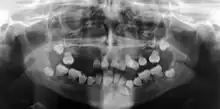

| Preoperative panoramic radiographs showing features of dentin dysplasia type I | |

Dentin dysplasia (DD) is a rare genetic developmental disorder affecting dentine production of the teeth, commonly exhibiting an autosomal dominant inheritance that causes malformation of the root. It affects both primary and permanent dentitions in approximately 1 in every 100,000 patients.[1] It is characterized by the presence of normal enamel but atypical dentin with abnormal pulpal morphology. Witkop[1] in 1972 classified DD into two types which are Type I (DD-1) is the radicular type, and type II (DD-2) is the coronal type. DD-1 has been further divided into 4 different subtypes (DD-1a,1b,1c,1d) based on the radiographic features.[2]

In other words, affected primary teeth usually have abnormal -shaped or shorter than normal roots. “Crescent/half-moon shaped” pulp chamber remnant in permanent teeth can be seen on x-rays. The roots may appear to be darker or radiolucent/pointy and short with apical constriction. Dentine is laid down abnormally and causes excessive growth within the pulp chamber. This will reduce the pulp space and eventually cause incomplete and total pulp chamber obliteration in permanent teeth.[12][13] Sometimes periapical pathology or cysts can be seen around the root apex.[11] Most cases of DD associated with peri-apical radiolucency/ pathology have been diagnosed as radicular cysts, but some of them have been as diagnosed peri-apical granuloma instead.[14]